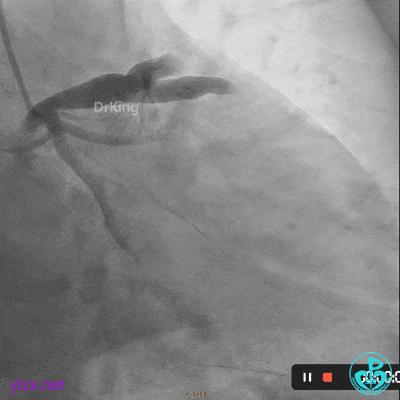

03 急诊冠脉造影

右冠脉粗大,近中段瘤样扩张明显,中段闭塞,局部可见大块血栓影。

前降支开口至近段明显瘤样扩张,中段闭塞,第一对角支粗大,无明显狭窄。

LCX发育小,内膜不光滑,血流3级。

首选开通右冠脉,导丝到达闭塞段远端,球囊扩张后,可见大量血栓,抽吸导管反复抽吸出大量血栓。冠脉内推注尿激酶原20mg,复查造影提示右冠脉远端显影,调整导丝至远段。

球囊再次扩张闭塞段,并对后降支及左室后支开口行对吻球囊扩张,复查造影示血流3级,无夹层行成,右冠脉远段仍可见血栓影。